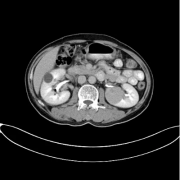

尹先生因长期从事体力劳动,前几年出现左下肢酸胀、乏力。因为当时症状不重,并为引起重视,没有做任何治疗。随着时间的流逝,尹先生病情逐渐加重,大隐静脉扩张、部分呈团块状,并伴有疼痛,活动起来极为不方便,已经不能正常工作了。经当地医院检查,尹先生曲张血管内已形成血栓,患者因惧怕手术,选择药物及打针治疗,腿部疼痛时好时坏,在与病痛多年的抗争中,曾诱发肺栓塞,险些丧命。

尹先生意识到了问题的严重性,经多方面考察、权衡,选择来济南中医静脉曲张医院接受超微创取栓治疗,并通过微创手术将其静脉曲张隐患一并消除,体内埋藏的“定时炸弹”排除了,腿酸、腿胀的症状也消失不见,已完全康复,至今无复发现象,得到尹先生及家人的一致好评。